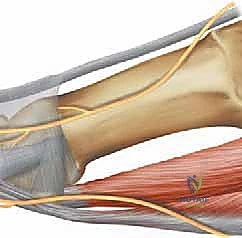

Identifying the Plantar Medial Cutaneous Nerve: This is arguably the most critical step in the initial dissection. The plantar medial cutaneous nerve, a terminal branch of the medial plantar nerve, typically runs along the inferior border of the abductor hallucis muscle tendon, adjacent to the MTP joint capsule.

- Use fine blunt dissection with Metzenbaum scissors or a small hemostat. Gently spread the tissues to visualize the nerve. It will appear as a yellowish, delicate structure.

- Protection: Once identified, meticulously mobilize the nerve. We will retract it inferiorly, away from our surgical field. Some surgeons prefer dorsal retraction, but inferior retraction often provides a clearer path to the sesamoid.

- Vessel Loop: For enhanced protection and clear visualization, carefully place a thin vessel loop around the nerve. This allows for controlled retraction and acts as a constant reminder of its location.

- Surgical Warning:

> Surgical Warning: The plantar medial cutaneous nerve is highly susceptible to injury during this approach. Direct trauma, excessive traction, or entrapment can lead to debilitating neuritic pain postoperatively. Always identify, mobilize, and protect this nerve meticulously.